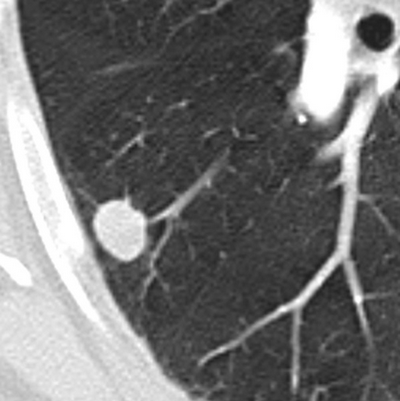

CT报告的肺肉芽肿性结节,多表现为实性结节,可单发可多发,边界模糊。

图1. 肺肉芽肿性结节,边缘光滑清晰

(图片来自:Evaluation of solitary pulmonary nodule detected during computed tomography examination